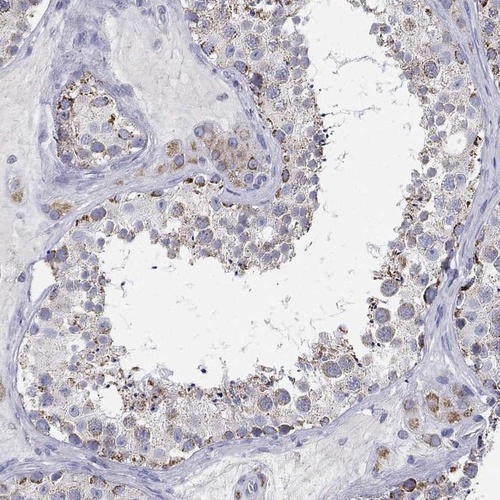

Immunohistochemical staining of human testis shows moderate cytoplasmic positivity in cells in seminiferous ducts and Leydig cells.